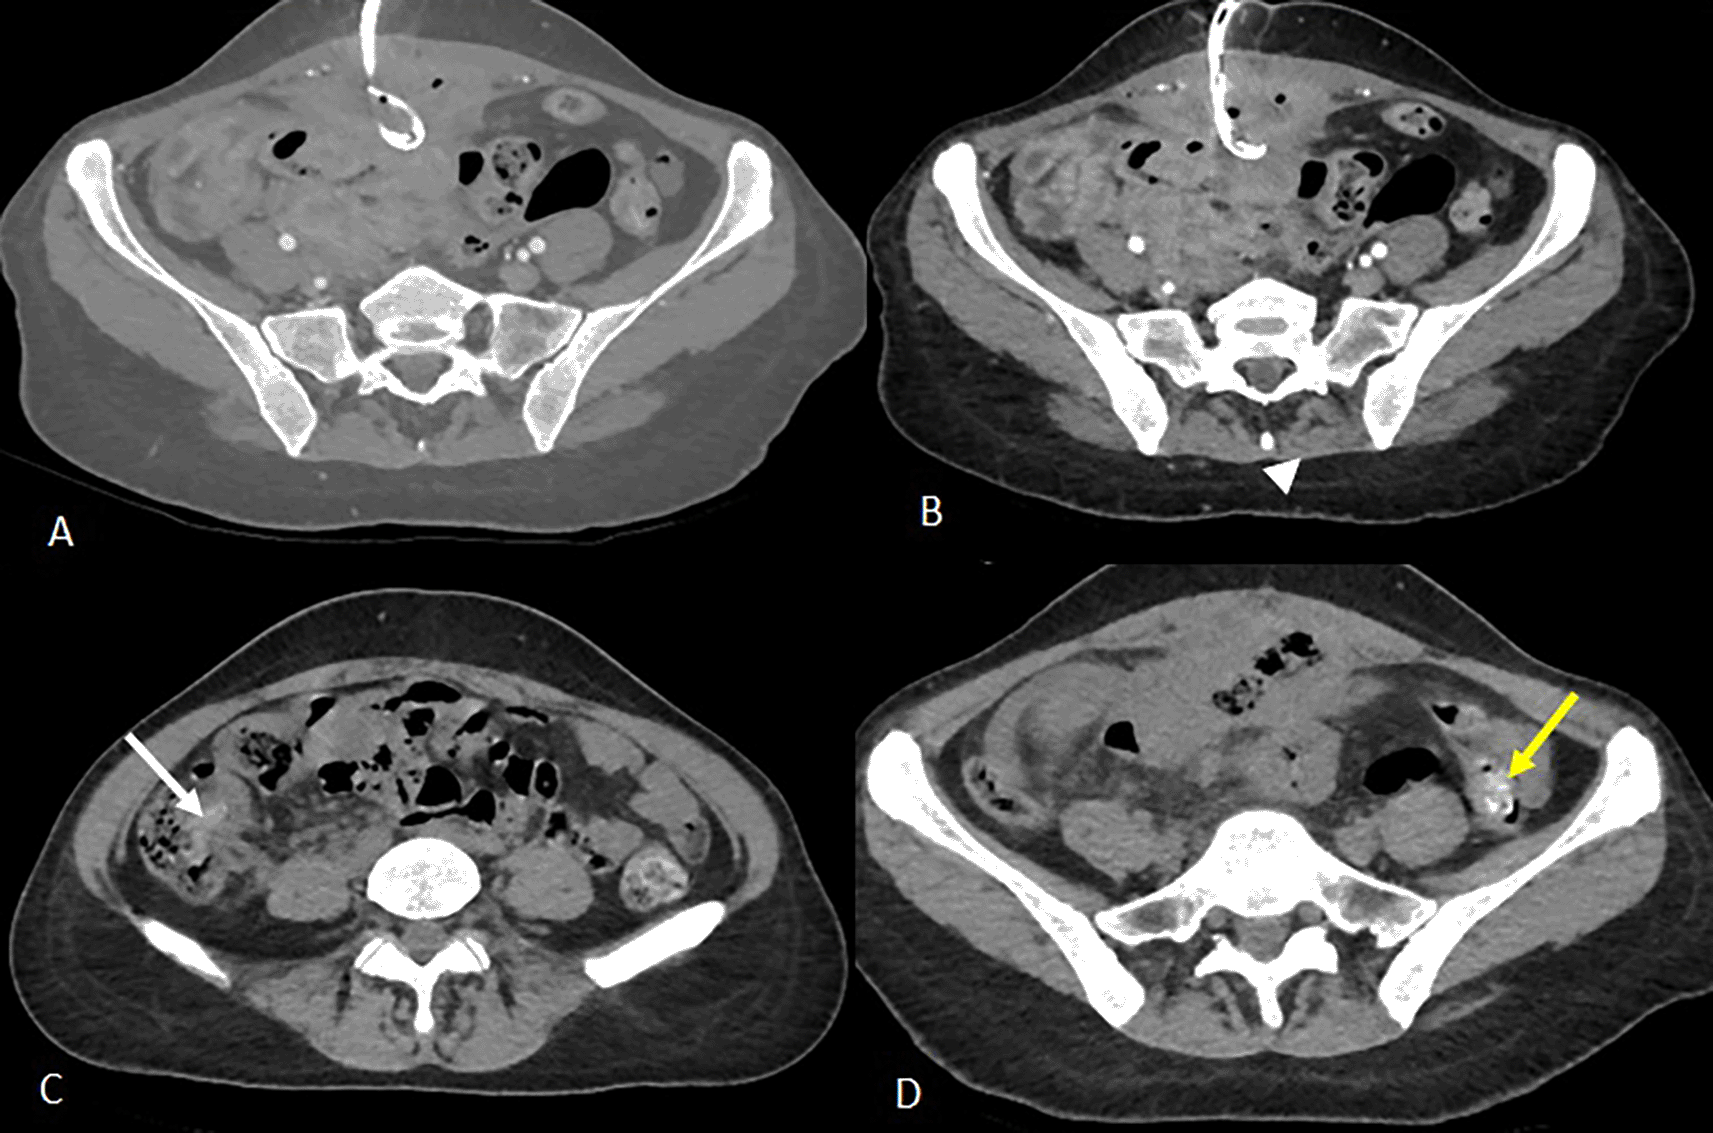

Empirical broad-spectrum antibiotic therapy with imipenem was initiated. On day 3, a radiologically guided percutaneous drainage of the collection was performed (Figure 2), yielding a small volume of fecal material. Despite drainage, CRP rose to 140 mg/L and stabilized at 120 mg/L.

Axial slices after portal vein injection (A, B) show a drain in place with its distal end coiled in the collection (A), a stable appearance of the digestive wall thickening and the peritoneal reaction in the surrounding area previously described (B).

Axial slices of the abdominal-pelvic CT scan without injection of contrast medium C and D show the migration of the two intraluminal foreign bodies from the ileal loops visualised on the previous scan. The first foreign body is found in the caecum (image C, white arrow) and the second in the left colon with its distal end in the sigmoid colon (image D, yellow arrow).